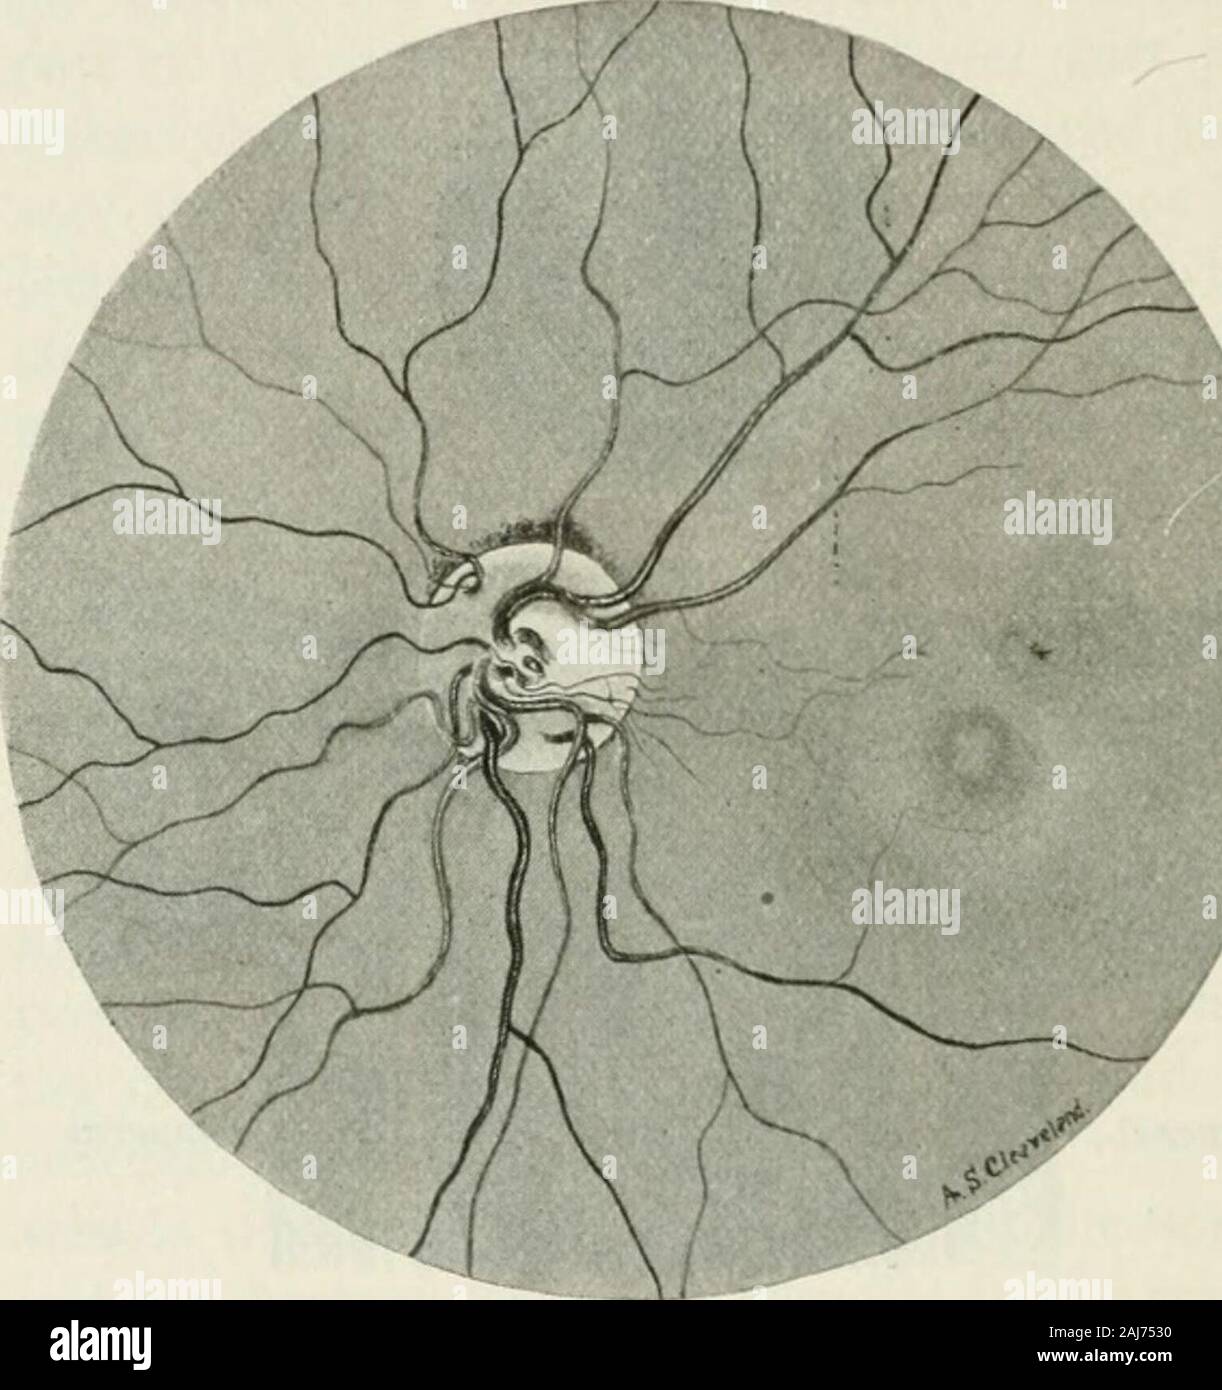

From www.alamy.com

The commoner diseases of the eye how to detect and how to treat them Optic Nerve Eye Conditions these conditions can damage an optic nerve and affect your vision: Optic neuritis is when something (usually inflammation) disrupts signals traveling through your optic nerve. Fluid buildup near the front of your eyes can put pressure on. glaucoma is a group of eye conditions that damage the optic nerve. The optic nerve sends visual information from your eye. Optic Nerve Eye Conditions.